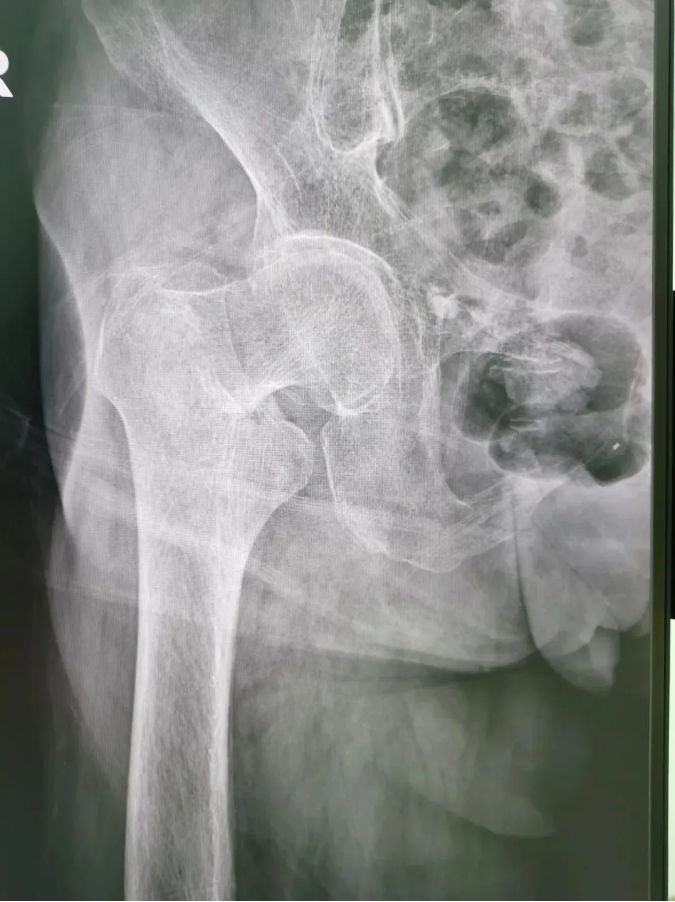

術(shù)前X光

今年91歲的陳婆婆,9月份時(shí)在家不慎摔倒,右臀部著地,當(dāng)下感到髖部劇烈疼痛并活動(dòng)受限。為求進(jìn)一步治療,到順德和平外科醫(yī)院骨三區(qū)就診,該區(qū)主任楊升平主任為其診療,被診斷為“右股骨頸骨折”,需進(jìn)行右股骨頸骨折經(jīng)皮閉合復(fù)位空心螺釘內(nèi)固定手術(shù)。